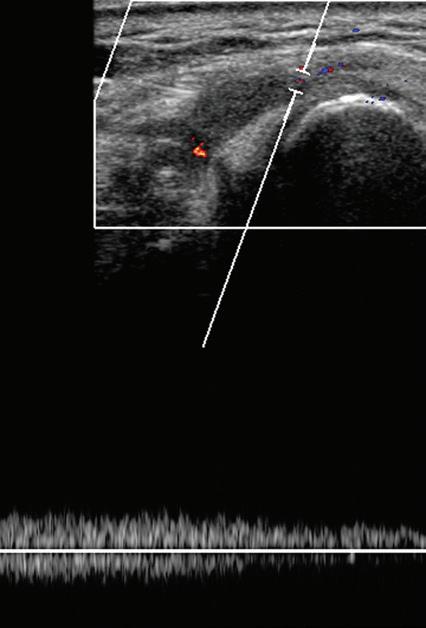

COLOR AND POWER DOPPLER

Most ultrasound machines include color and power Doppler imaging capabilities, with possible spectral waveform analysis. Ultrasound uses the Doppler effect, in which the sound frequency of an object changes as the object travels toward or away from a point of reference, to obtain information about blood flow. Color flow imaging shows

colored blood flow superimposed on a gray-scale image, in which two colors such as red and blue represent flow toward and away from the transducer, respectively (Fig. 1.28).24 Pulsed-wave or duplex Doppler ultrasound displays an ultrasound image and waveform (Fig. 1.29). There are important considerations to optimize the Doppler ultrasound. Reducing the width of the field of view and increasing the frame rate are helpful. To correct for aliasing (when the Doppler shift frequency of blood is greater than the detected frequency, which causes an error in frequency measurement), one can increase the pulse repetition frequency, lower the ultrasound frequency, or increase the angle between the sound beam

and the flow direction toward perpendicular. Power Doppler is another method of color Doppler ultrasound that is generally considered more sensitive to blood flow (it shows small vessels and slow flow rates) compared with conventional color Doppler, although significant variability exists depending on the ultrasound machine.25 Unlike conventional color Doppler, power Doppler assigns a color to blood flow regardless of direction (Fig. 1.30) and is extremely sensitive to movement of the transducer, which produces a flash artifact. The color gain should be optimally adjusted for Doppler imaging to avoid artifact if the setting

is too sensitive and for false-negative flow if sensitivity is too low. To optimize power Doppler imaging, set the color background (without the gray-scale displayed) so that the lowest level of color nearly uniformly is present, with only minimal presence of the next highest color level.26